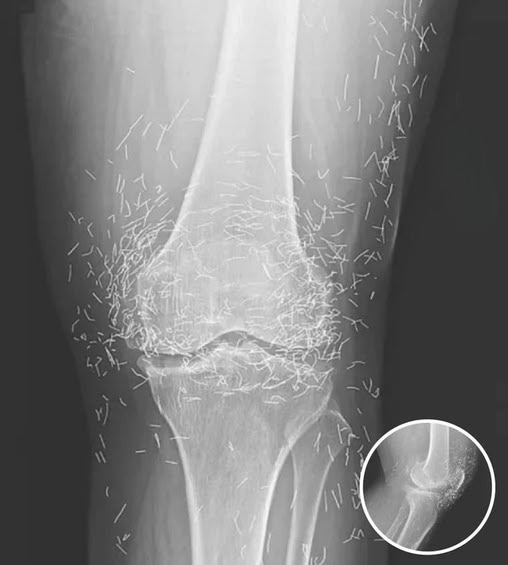

A routine medical scan in South Korea revealed a surprising and concerning finding. A 65-year-old woman, seeking treatment for ongoing knee pain, discovered that her joint tissue contained hundreds of tiny gold needles. What had been assumed to be ordinary discomfort from osteoarthritisโa condition associated with stiffness, swelling, and cartilage breakdownโturned out to involve something…